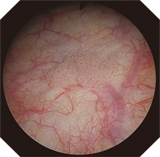

HDTV image

Narrow Band Imaging (NBI) is the World's Only Patented Endoscopic Light Technology for enhancing the visualization of vascular structures without the use of dyes, drugs, or contrast agents. NBI, which is strongly absorbed by hemoglobin and penetrates only the surface of tissues, is ideal for highlighting areas of increased vascularity. As a result, under NBI, capillaries on the mucosal surface are displayed in brown on the monitor, and veins in the submucosa are displayed in cyan. NBI is simple to use. With no dyes or drugs, no time limit of effectiveness, and no added cost, NBI is an easy addition to your standard procedure work flow.